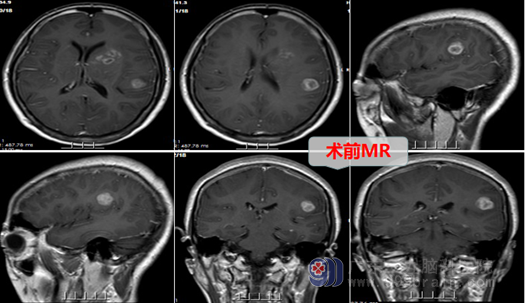

入院后,欧阳辉主任组织外十科团队尽快给陈姐完善了各项术前检查和准备工作,我院MR示:左侧额顶叶占位病变:高级别胶质瘤可能性大。欧阳主任团队于2022年10月17日为陈姐进行了“左侧额顶叶胶质瘤切除术”,术中冰冻病理及后期常规病理报告证实为:高级别胶质瘤。术后患者神志清醒,回答正确,四肢活动都是很好的,也没有出现其他并发症。